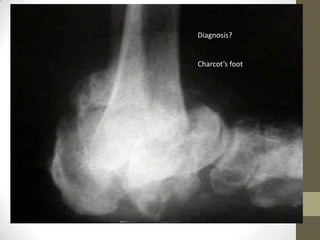

Diagnosis?

Charcot’s foot